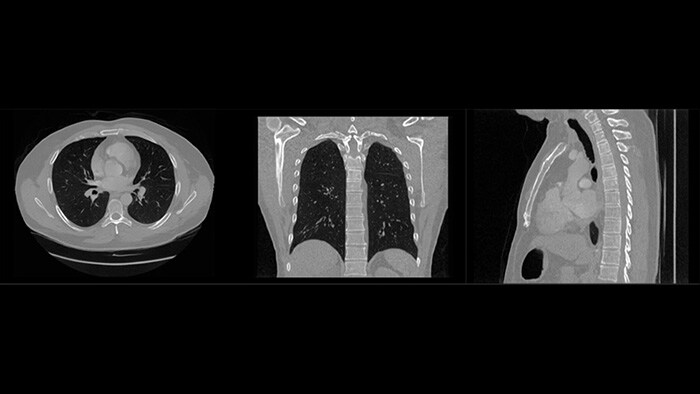

Philips receives FDA 510(k) clearance for its Rembra platform, expanding access to faster, more precise CT imaging across frontline care and cancer treatment planning

Click here to learn morePhilips receives FDA 510(k) clearance for Verida, the world’s first AI-powered detector-based spectral CT*, advancing diagnostic precision across clinical applications